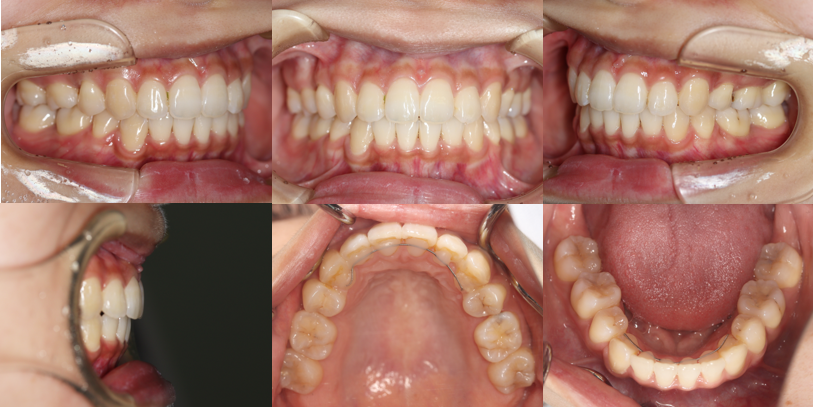

上下顎前突(やや口ゴボ)+叢生(歯のガタガタ)+過蓋咬合(かみ合わせが深い)

After

| 処置内容: | 上顎右側第二小臼歯・左側第一小臼歯、下顎両側第一小臼歯を抜歯 マルチブラケット装置による表側の全顎矯正(ホワイトシステム) 歯科矯正用アンカースクリュー(インプラントアンカー) |

| 費用: | (矯正装置料+全調整料+保定装置料+消費税):770,000円 |

| メリット: | 口元が後退し、横顔がきれいになる 口が閉じやすくなる 歯のガタガタが改善され、嚙み合わせが緊密になる 歯みがきがしやすくなり、むし歯や歯周病にかかりにくくなる |

| デメリット: | 永久歯を抜歯する 治療期間が長期間にわたる 治療中は時間をかけて歯みがきをしっかりする必要がある |